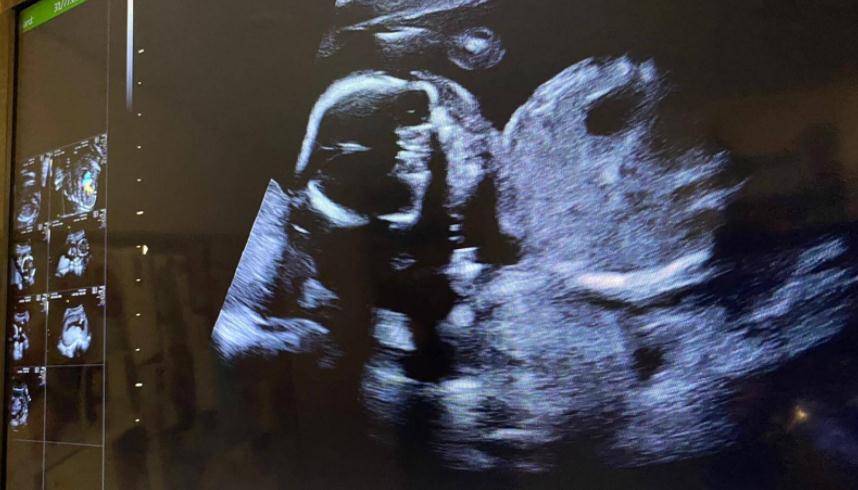

时隔一个月 , 黎诺懿终于愿意公布好消息了 。 他透露 , 妻子目前已怀孕19周 , 差不多4个月了 。 由于妻子有过怀孕经验 , 这一次很少孕吐 。